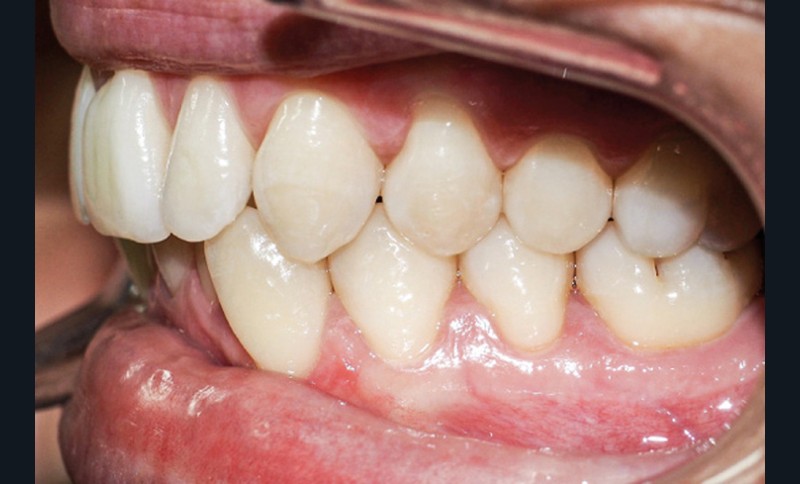

Discussion (fig. 4 à 7)

La durée du traitement a été de vingt-trois mois. Des mouvements lents ont permis un contrôle des axes incisifs mandibulaires.

Le stripping maxillaire a permis :

- de rééquilibrer les dimensions entre les incisives centrales et latérales (DDD initiale par insuffisance maxillaire) ;

- d’éviter l’apparition de triangles noirs entre les incisives [3] ;

- d’éviter la présence d’un surplomb résiduel.

Des triangles noirs sont apparus à la mandibule suite à l’extraction de 31 : ils ne sont pas exposés lors du sourire, ce qui n’entraîne pas de défaut esthétique.

La génioplastie discrète apporte un équilibre facial et une fermeture labiale non forcée, ce qui limite le risque de récidive liée à la pression musculaire.

La superposition des structures anatomiques nous montre une ingression de l’incisive mandibulaire et un maintien de l’axe ainsi qu’une distalisation en gression de l’incisive maxillaire.